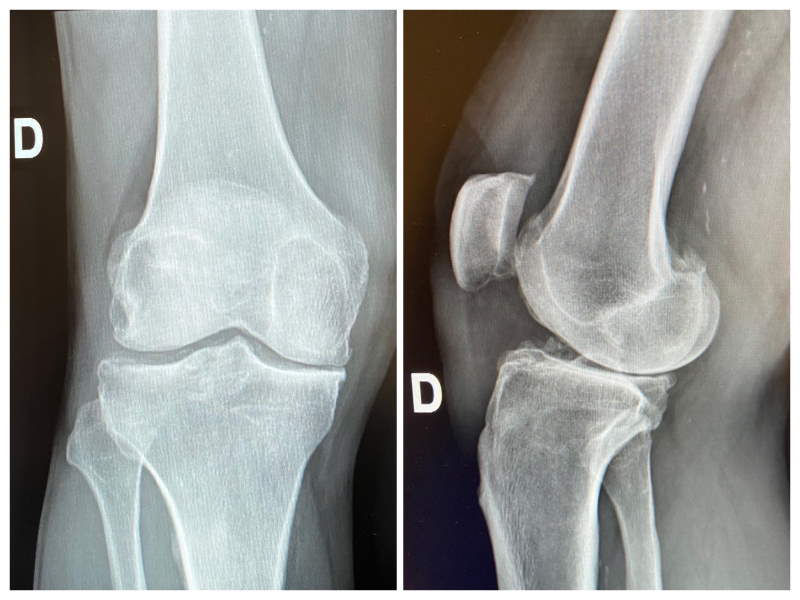

Radiografia Ginocchio

Che cos'è la Radiografia del Ginocchio?

La radiografia del ginocchio è un esame diagnostico che utilizza raggi X per ottenere immagini dettagliate dell'articolazione del ginocchio.

Questo esame permette di visualizzare le ossa del ginocchio, inclusi il femore, la tibia, il perone, e le strutture circostanti

Le immagini radiografiche possono rivelare fratture, lussazioni, usura della cartilagine e altre anomalie ossee.